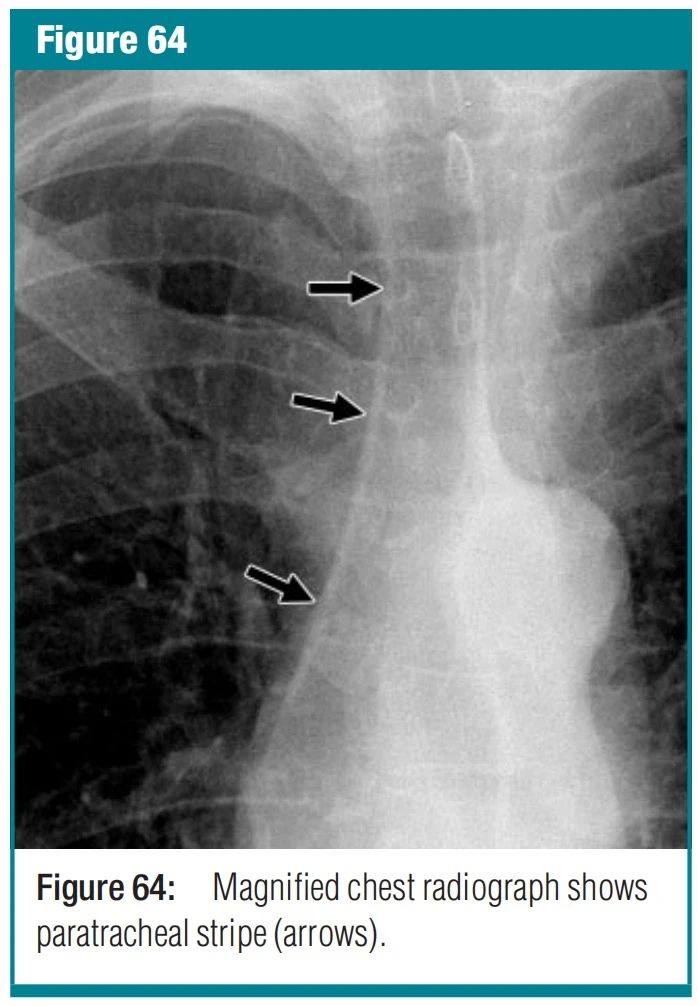

图12 right paratracheal stripe-右侧气管旁带 解剖学和 X 光片-右侧气管旁条纹是垂直、线性、软组织混浊,宽度小于 4 毫米。它对应于右气管壁、邻近的纵隔组织和邻近的胸膜。该条纹高 3-4 厘米,从大约锁骨内侧端的水平延伸到正面胸部 X 光片上的右侧气管支气管角。高达94% 的成年人可见,但纵隔脂肪丰富的个体会扩大或不存在。该条纹变宽、变形或消失的最常见病理原因是气管旁淋巴结肿大。